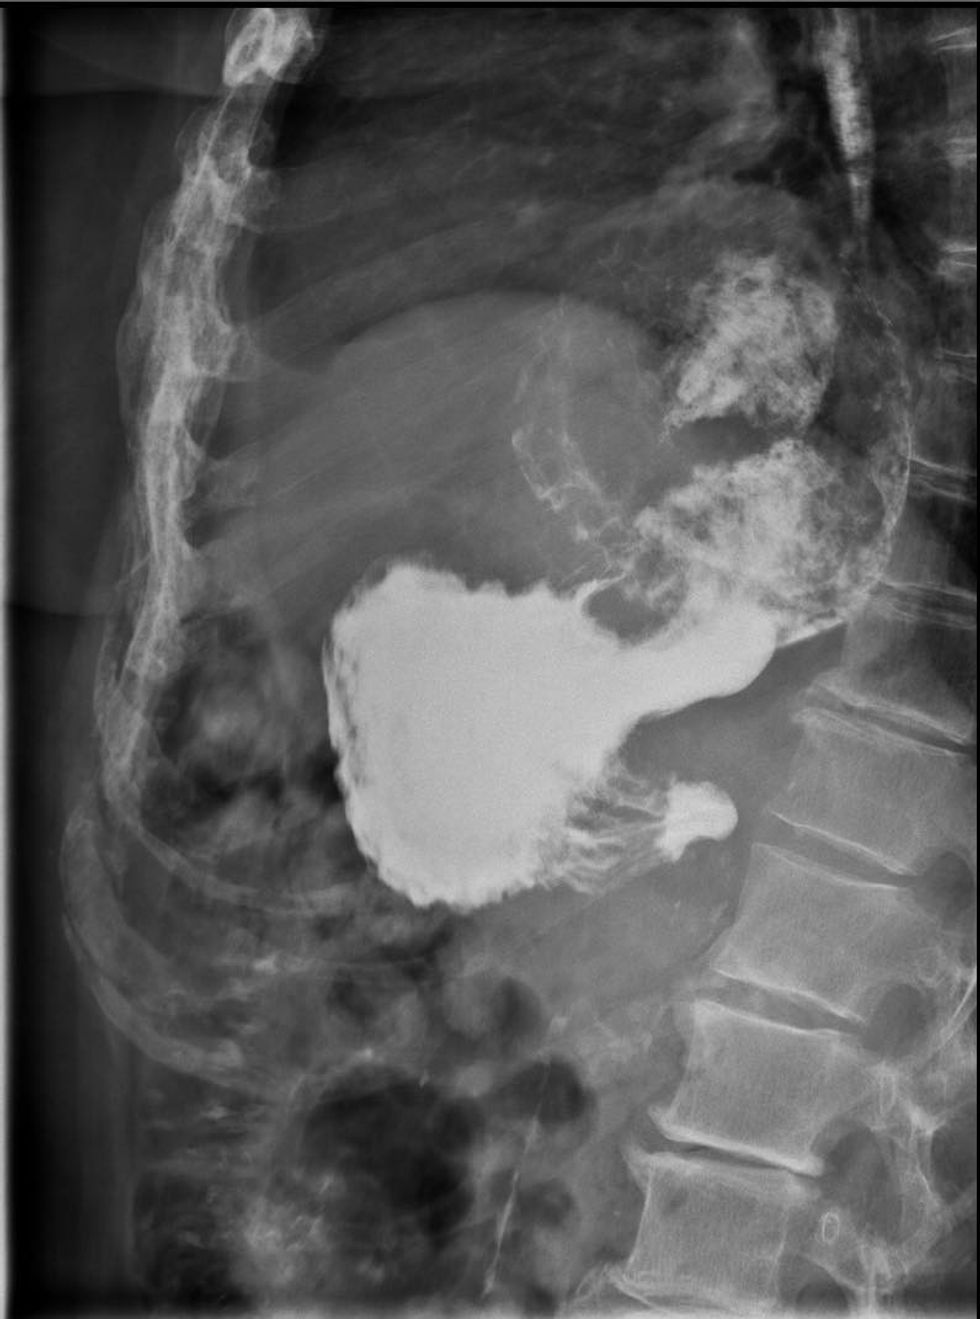

Sipas njoftimit, bëhet fjalë për sëmundjen jo të zakontë ku një pjesë e lukthit nga hapësira abdominale kalon në hapësirën torakale e në këtë rast, e komplikuar me përdredhje të lukthit rreth vetës duke shkaktuar rrezik për jetën e pacientit.

“Diagnozat si në vijim: Hernia hiatalis cum Volvulus ventriculi, Ileus et adhensionem dhe Peritonitis serosa, ku është realizuar nderhyrja operatore, Hernioraphia cum fundoplicatio sec. Nissen, Adhaesiolysis dhe Gastropexia”, thuhet në njoftim.